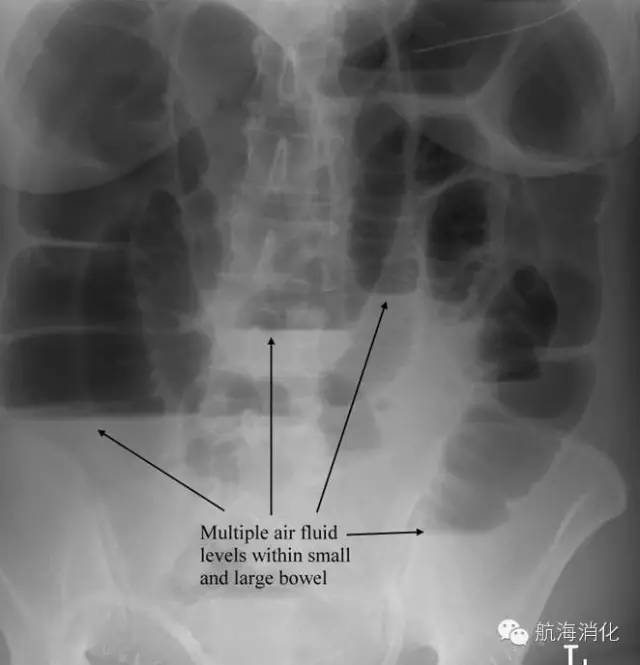

9.为什么要反复拍腹部X光片?

任何不明原因的腹痛,应常规腹部平片检查。腹痛后4-6小时出现气液平和明显肠管积气扩张时,即可诊断肠梗阻,同时,还可区别是小肠梗阻还是大肠梗阻、机械梗阻还是麻痹梗阻,动态观察可反映肠梗阻的病情变化,因此,肠梗阻发生后最好每1-3天拍一张腹部平片,直到气液平和肠积气消失。

机械性肠梗阻